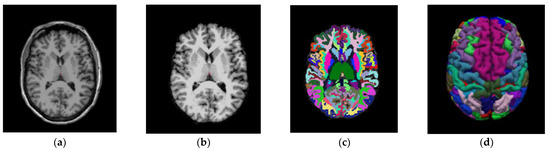

3.1. Obtention of Imaging Derived Features after PVC

This part of the method deals with the obtention of the different SUVR values, obtained for all ROIs in the images by applying several PVC methods. The imaging pipeline has a double path, one for processing the PET studies and another for the MRI studies. The MRI path is devoted to obtaining the ROI to compute the SUVR values on the PET after PVC correction. For this purpose, the Desikan–Killiany atlas [35] was employed, Figure 3 shows the different stages of the MRI process [32]. The atlas color labels [35] are shown in Figure 3c,d.

Figure 3. Coronal image of a patient from the study. (a) T1-weighted Magnetic Resonance Imaging (MRI—T1W). (b) MRI output after processing stages: Motion Correction and Conform, Intensity Normalization, Remove Neck and Skull Strip. (c) MRI output after applying Talairach transform computation and Cortical Parcellation Desikan-Killiany, an atlas that will permit us to obtain the values of Standard Uptake Value Ratio (SUVR) on the same patient from the PET image. (d) Three-dimensional reconstruction of the atlas from (c) using the color map of Desikan-Killiany atlas.